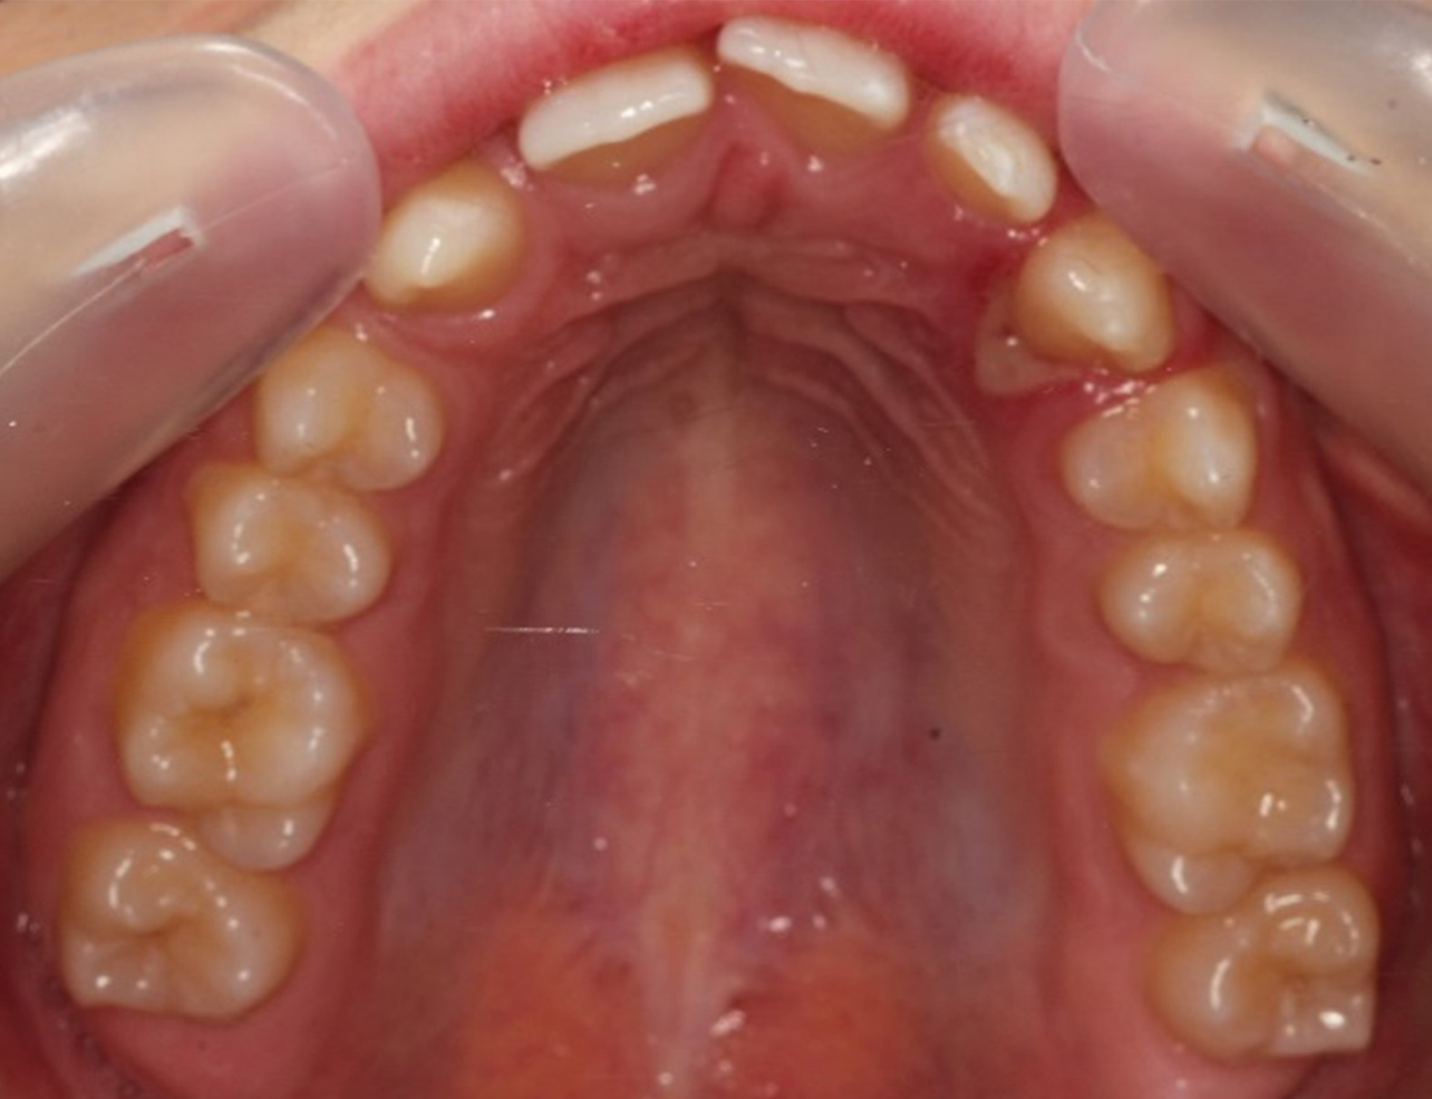

Skeletal Class II due to mandibular retrognathia, proclination of maxillary incisors, narrow arch creating a V-shaped arch, agenesis of 12, 31, 41, hyperdivergent facial pattern, moderate deep bite (2 mm), increased overjet (9 mm), asymmetric canine and molar Class II due to mandibular deviation to the left, maxillary midline deviation related to agenesis of 12, distal rotation of 35 and 45, and pronounced lower curve of Spee.

Upper arch: 20 active aligners

Transverse expansion

Derotation with mesial-out of first molars

Space opening for 12 by distalizing 13

Maxillary midline correction